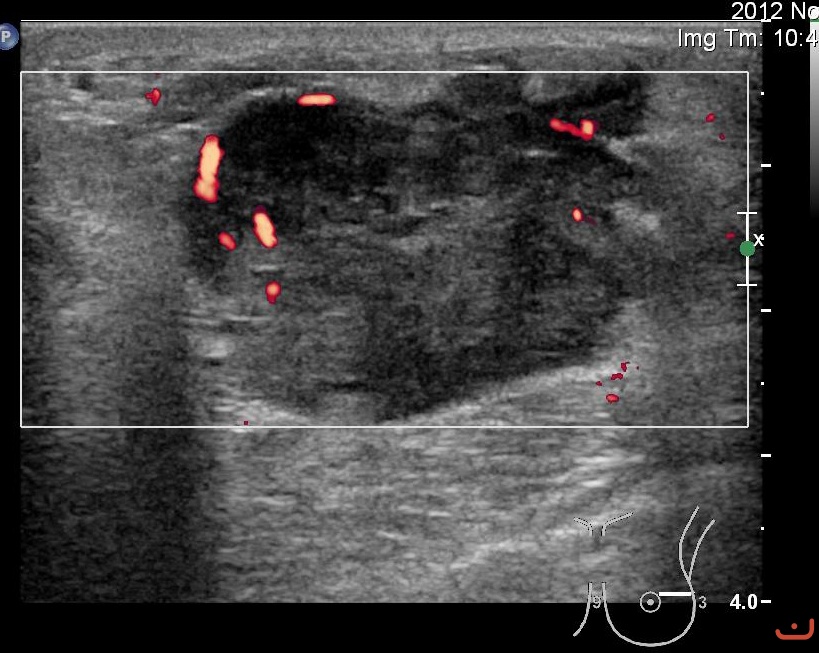

Malignant solid mass